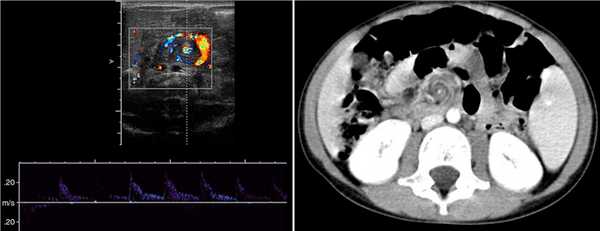

Незавершенный поворот средней кишки предрасполагает к завороту брыжейки тонкой кишки по часовой стрелке вокруг ВБА. В центре заворота расположена ВБА, а расширенная ВБВ образует характерное сосудистое кольцо — знак «водоворота». В головной части «водоворот» сформирован сосудами брыжейки; здесь четко видно ВБА. В хвостовой части «водоворот» сформирован петлями кишечника и венами брыжейки; ВБА может быть не видна.

Рисунок. На УЗИ и КТ справа от средней линии живота определяется характерный для заворота кишок знак «водоворота» с ВБА (стрелка) в центре и сосудистым кольцом из ВБВ (треугольник).

В большинстве случаев «водоворот» определяется справа, реже по центру и очень редко слева от средней линии живота. Размер «водоворота» у новорожденных 15-20 мм, у старших детей 40 мм. Часто брыжейка утолщена: в норме у детей раннего возраста расстояние от задней поверхности левой доли печени до аорты менее 1 см, а у детей с заворотом — 3-4 см. Также можно увидеть множественные мезентериальные лимфоузлы и некоторое количество выпота в брюшной полости.

Достоверно определить на сколько оборотов произошел заворот на УЗИ сложно. Если ВБВ в структуре «водоворота» расширена до 3-4 мм, то заворот сопровождается выраженным венозным застоем, и обычно составляет 1,5-2 оборота (540°-720°). Если расширенных вен в структуре «водоворота» нет, то заворот нетугой — на 0,5-1 оборот (180°-360°). Некоторый личный опыт позволяет достаточно точно определить количество оборотов, если проследить заворот в кранио-каудальном направлении.

Рисунок. Ребенок с признаками высокой кишечной непроходимости. На УЗИ справа от средней линии живота определяется знак «водоворота». Заключение: Эхо-признаки заворота кишок.